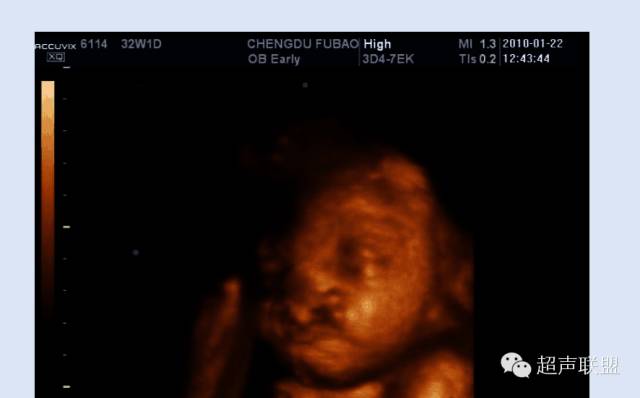

近年来,颜面部结构的辨认与颜面部畸形的产前超声诊断越来越受到人们的重视,三维超声的飞速发展,能将颜面部结构及畸形非常逼真地展现在人们面前。随着超声仪器的不断发展,图像分辨力的不断提高,颜面部的许多细小结构及某些面部表情亦能清晰可辨,如胎儿人中的显示,胎儿争眼、皱额等细微表情动作的显示与观察等。眼眶、眼球、眼裂、眼睑、前额、鼻、鼻骨、上下唇、人中、上颌骨及上牙槽突与其内的牙胚、下颌骨及下牙槽突与其内的牙胚、下颌、硬腭、舌、口、颧骨、耳廊等结构均能清晰可辨,因此,对这些正常结构的正确认识,对提高颜面部结构畸形的认识是非常有帮助的。

(二)鼻唇冠状切面

1.扫查方法:声束从面部侧方进入,通过鼻、 上下唇及颏部,即可获得。

2.判断标准:可显示鼻的外形、双侧鼻孔、鼻翼、鼻柱、上唇及人中、上下唇唇红、颏部。此切面在筛查与诊断唇裂时很重要。

3.主要观察的解剖结构及内容:

(1)鼻:鼻的外形,鼻孔,左、右鼻翼是否对称;

(2)上、下唇及人中:人中是否存在,上唇是否连续完整。

4.临床意义:

该切面是筛查各种唇裂的常规切面,很多其他颜面部异常亦有明显表现,如无鼻、长鼻或喙鼻、裂鼻、双鼻、鞍鼻、单鼻孔、口角裂畸形、面斜裂畸形、口腔肿瘤、小下颌畸形、无下颌并耳畸形等。